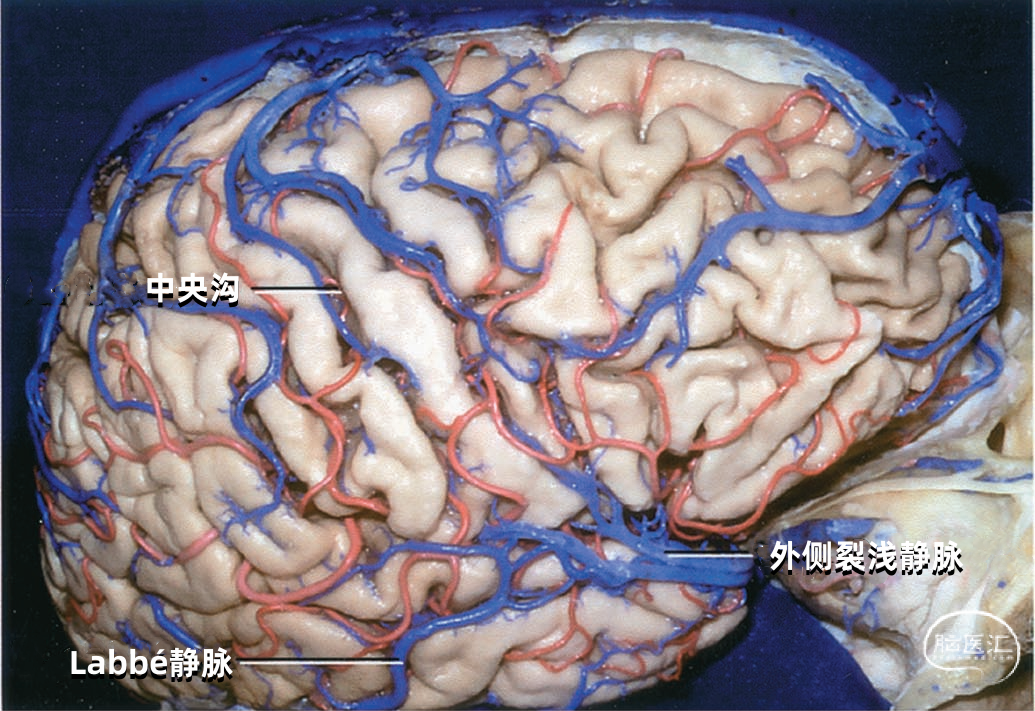

大脑外侧面最大的静脉是Trolard、Labbé、外侧裂浅静脉。 Trolard静脉是最粗大的吻合静脉,连接外侧裂静脉和上矢状窦。Labbé静脉则是连接外侧裂浅静脉和横窦的最粗大吻合静脉。外侧裂浅静脉沿外侧裂表面走行,而且主要沿蝶骨嵴汇入硬膜窦(蝶顶窦或海绵窦)。 虽然Trolard、Labbé静脉和外侧裂浅静脉大小可能相同,但更常见的是其中一支或两支血管比较粗大,而剩下的则细小甚至缺如。通常左右两侧血管的大小并不对称。

下图示三组吻合静脉,Trolard静脉和Labbé静脉为主要引流静脉。

▼2.Labbé静脉

Labbé静脉也称下吻合静脉,是跨越颞叶外侧,连接外侧裂与横窦之间的最大吻合静脉。它通常起自外侧裂中部,行向后下,进入横窦前部。 Labbé静脉经过颞叶表面的位置有可能非常靠后甚至位于颞叶的最后界,或非常靠前达颞叶前1/3的外侧面。在此研究的20例半球中,12例Labbé静脉位于颞中静脉水平,6例位于颞后静脉水平,2例位于颞前静脉水平。有时会有两条Labbé静脉,其中后支通常会粗大一些。

下图示右颞叶和外侧裂。外侧裂浅静脉的前部细小,而汇入Labbé的后部粗大。一支颞中静脉沿颞上沟形成一桥静脉,跨过半球下缘汇入小脑幕窦。外侧裂浅静脉还通过两条Trolard静脉与上矢状窦吻合:一条经过额叶,另一条经过顶叶。颞外侧裂静脉引流颞上回,汇入外侧裂浅静脉和颞中静脉。

下图示横窦和小脑幕窦的分支。抬起颞叶的后部,暴露进入横窦的Labbé静脉、颞后静脉和枕后静脉,从颞叶底面进入小脑幕窦的颞底静脉。